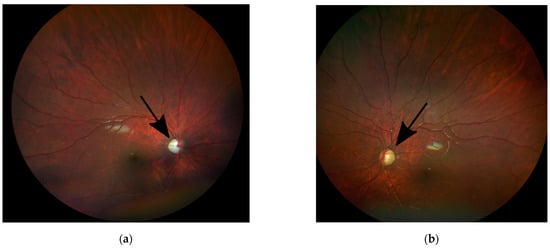

3.1. Case Description